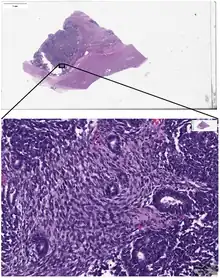

Whole slide scan of a Wilms' tumor.